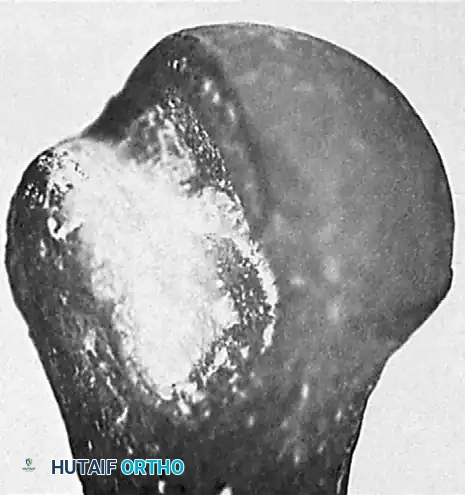

Posterior Dislocations:

In chronic posterior dislocations, a similar but reversed bony lesion is found. This is a compression fracture caused by the impingement of the posterior rim of the glenoid on the anteromedial aspect of the humeral head (often termed a "reverse Hill-Sachs" or McLaughlin lesion). Like their anterior counterparts, these lesions are usually massive due to the patient’s continual attempts to increase the range of motion against a fixed bony block.